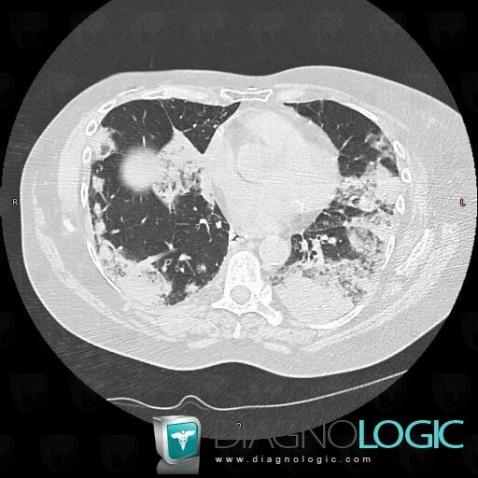

Bronchioloalveolar carcinoma, Pulmonary parenchyma, CT

Here is the specific information in the key image above:

- Diagnosis Bronchioloalveolar carcinoma, Location(s) Pulmonary parenchyma, with gamuts Multiple pulmonary masses